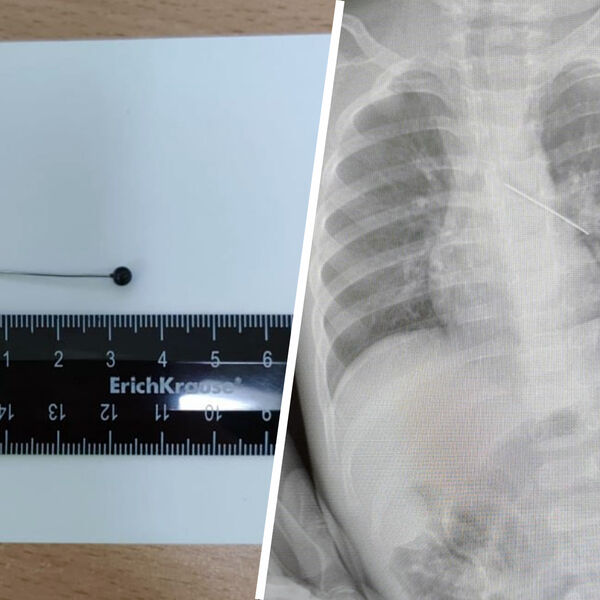

В ХМАО годовалый ребенок проглотил булавку

В Сургуте врачи спасли годовалого ребенка, проглотившего булавку

Врачи Центра охраны материнства и детства спасли 17-месячного ребенка, который из любопытства проглотил булавку. Об этом сообщила президент медицинского учреждения Лариса Белоцерковцева в Telegram-канале.

По словам медика, мать мальчика вовремя заметила беду и привезла ребенка в медицинское учреждение. Обследование показало, что инородный предмет зафиксировался в бронхах.

«Если бы бригада наших высокопрофессиональных специалистов не смогла удалить инородный предмет с помощью бронхоскопа, ребенка пришлось бы передавать торакальным хирургам для проведения большой операции», — пояснила Белоцерковцева.